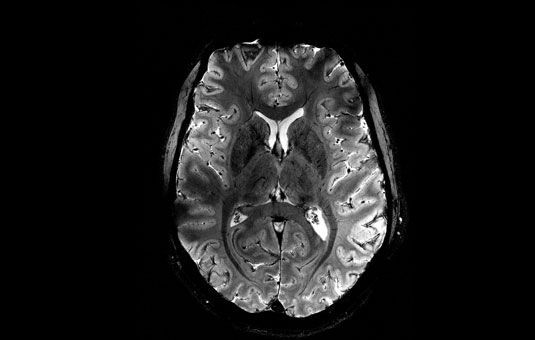

Os pesquisadores originalmente pretendiam acompanhar o desenvolvimento cerebral normal dos adolescentes ao longo do tempo, começando com ressonâncias magnéticas (RM) que realizaram nos cérebros dos participantes em 2018. Eles planejavam fazer outro exame em 2020.

A pandemia atrasou a segunda RM por um período de três a quatro anos — quando os 130 participantes, residentes no estado de Washington, tinham entre 12 e 20 anos. Os autores excluíram adolescentes que haviam sido diagnosticados com um transtorno de desenvolvimento ou psiquiátrico; ou que estavam tomando medicamentos psicotrópicos.

A equipe usou os dados de RM pré-pandemia para criar um “modelo normativo” de como 68 regiões do cérebro provavelmente se desenvolveriam ao longo da adolescência típica, para que pudessem comparar os dados de RM pós-pandemia e ver se eles se desviavam das expectativas. Esse modelo normativo é análogo às tabelas de crescimento normativas usadas nos consultórios pediátricos para acompanhar a altura e o peso das crianças pequenas, disseram os autores.

O estudo revelou um afinamento cortical acelerado nos cérebros pós-pandemia de adolescentes — ocorrendo em 30 regiões cerebrais em ambos os hemisférios e todos os lobos nas meninas, e em apenas duas regiões nos meninos. A prevalência do afinamento atingiu 43% e 6% das regiões cerebrais estudadas para meninas e meninos, respectivamente.